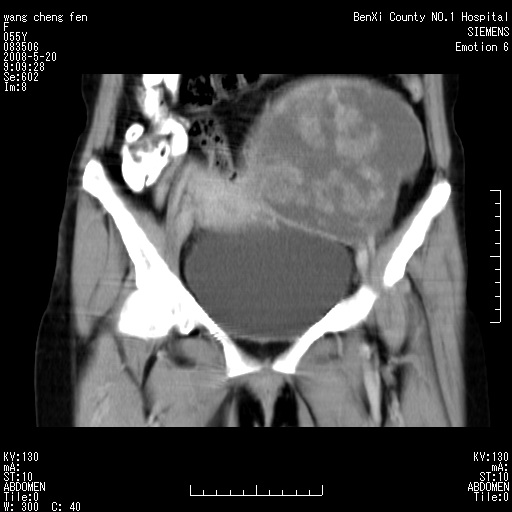

标题: CT3539:盆腔巨大肿瘤增强 [打印本页]

标题: CT3539:盆腔巨大肿瘤增强

女、绝经后阴道流血3个月

左侧附件区巨大囊实性病灶,边缘光整,病灶囊壁较厚,增强示囊壁及实性部分明显强化,强化呈度与宫体实质大致相同,宫腔积液征像,未见盆腔积液等其他异常,考虑左侧卵巢囊腺癌,不除外囊腺瘤及浆膜下肌瘤坏死

左侧附件区巨大囊实性病灶,边缘光整,病灶囊壁较厚,增强示囊壁及实性部分明显强化,强化呈度与宫体实质大致相同,宫腔积液征像,未见盆腔积液等其他异常。绝经后阴道流血3个月,结合病史左侧卵巢囊腺癌首先考虑,宫腔扩大不除外累及。期待结果。

考虑巨大的浆膜下子宫肌瘤并变性坏死,宫颈周围静脉曲张。

囊实性肿块分隔厚度较大,厚薄不均,增强实性成分明显强化,有不规则阴道流血,卵巢囊腺癌可能性大。